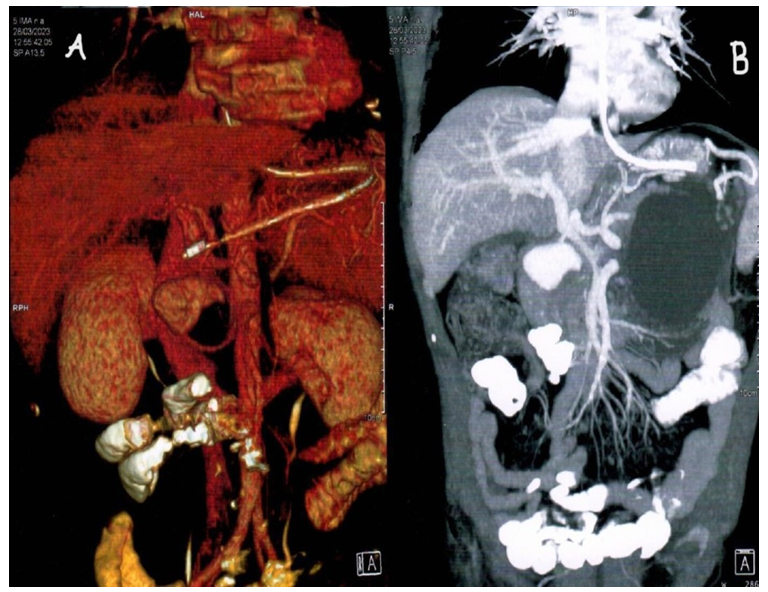

Contrast enhanced computer tomography suggestive of generalised atrophic pancreas with periphery enhancing cystic lesion of size 11.6*10.5*10.2 cm.

In distal pancreatic body. There is evidence of intensely enhancing lesion of size 2.7*3.6*3.8 cm noted in upper abdomen adjacent to head of pancreas and duodenum. This lesion is seen in continuation with the gastroduodenal branch of common hepatic artery suggestive of arterial aneurysm (Figure 2).

Figure 2: CECT images with vascular reconstruction showing pancreatic pseudocyst with GDA aneurysm.

2A: Vascular reconstruction of computed tomography demonstrating gastroduodenal artery aneurysm; 2B: CECT image demonstrating pancreatic pseudocyst with GDA aneurysm.